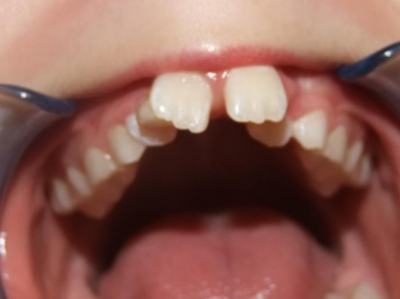

Leeftijd bij aanvang: 9 jaar

1-6 Bonded Hyrax + volledig vast onderkaak + TransForce onderkaak

7-13 Twin Block

14-28 volledig vast onder- en bovenkaak + rotator

Retentie: Wrap-Around

Leeftijd bij retentie: 12 jaar